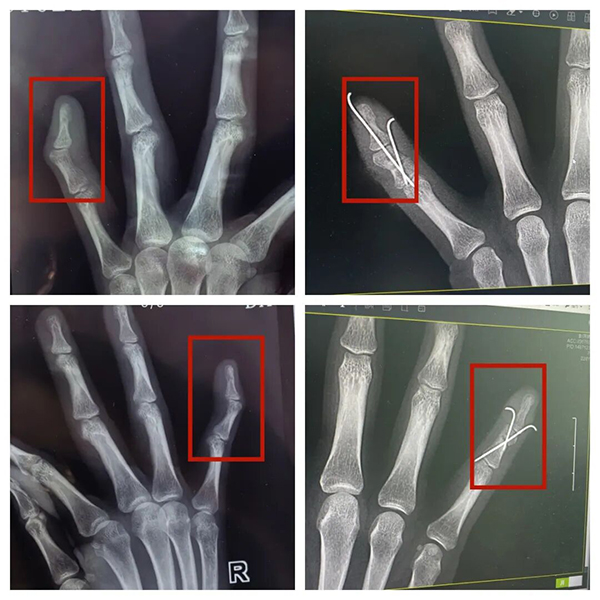

手指骨楔形截骨术(双侧)+指骨钢针内固定术

线上初步评估后,小莉与吴医生约好了线下门诊进一步检查。在全面细致的检查与评估后,考虑到她的手指畸形时间长,骨骼发育已经定型,经过细致严谨的术前讨论,吴医生在与小莉及家属充分沟通后,最终制定个性化的楔形截骨+钢针内固定方案。他表示,“我们主要通过精准的截骨角度调整,能够最大程度地恢复手指的正常力线与外观,同时利用钢针内固定保证截骨端的稳定愈合。”

整个手术过程一气呵成,出血少、损伤小,完美实现了预期的矫形目标。看着自己恢复的正常小指,埋藏在小莉心里的28年的“心结”终于打开了,她的脸上也露出了灿烂的笑容,言语间更是充满了感激:“真的太谢谢你们了,不仅仅技术好,服务态度也很好,这下我心里的石头终于可以落地了。”